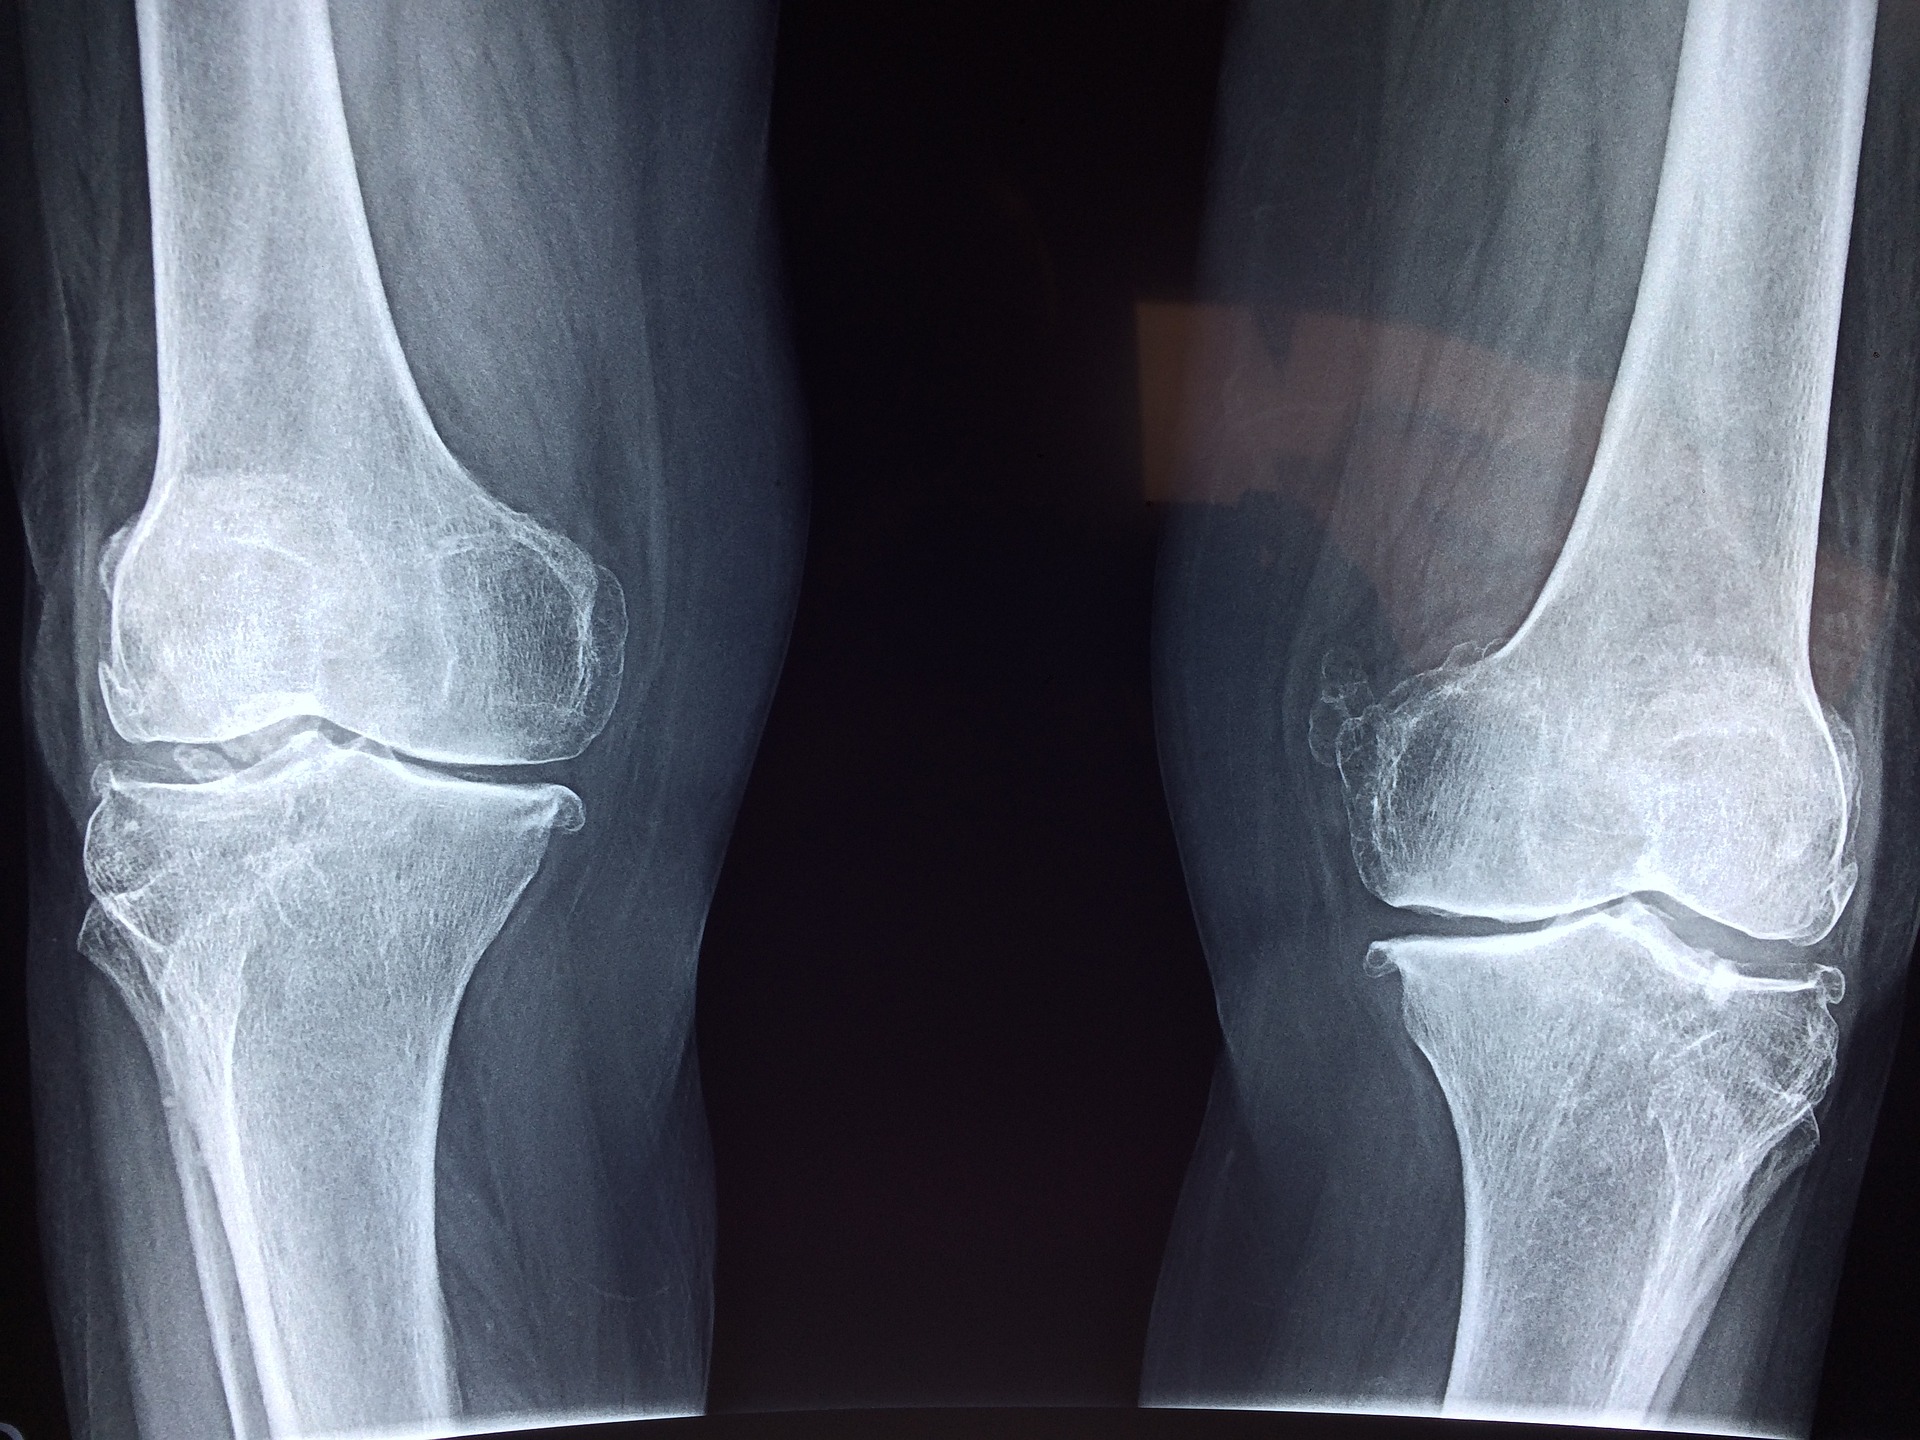

La mayoría está en los huesos, formando parte del osteocito, que es la célula ósea por excelencia. (Foto Prensa Libre: Dr. Manuel González Reyes en Pixabay)

La mayoría está en los huesos, formando parte del osteocito, que es la célula ósea por excelencia. Es como otra cualquiera, pero su matriz está mineralizada. Es decir, endurecida por la presencia de minerales. A la cabeza están el calcio, el magnesio, el fósforo y el zinc, entre otros.

El 95% del calcio está en huesos y dientes. El resto está distribuido en músculos, corazón y otros órganos.